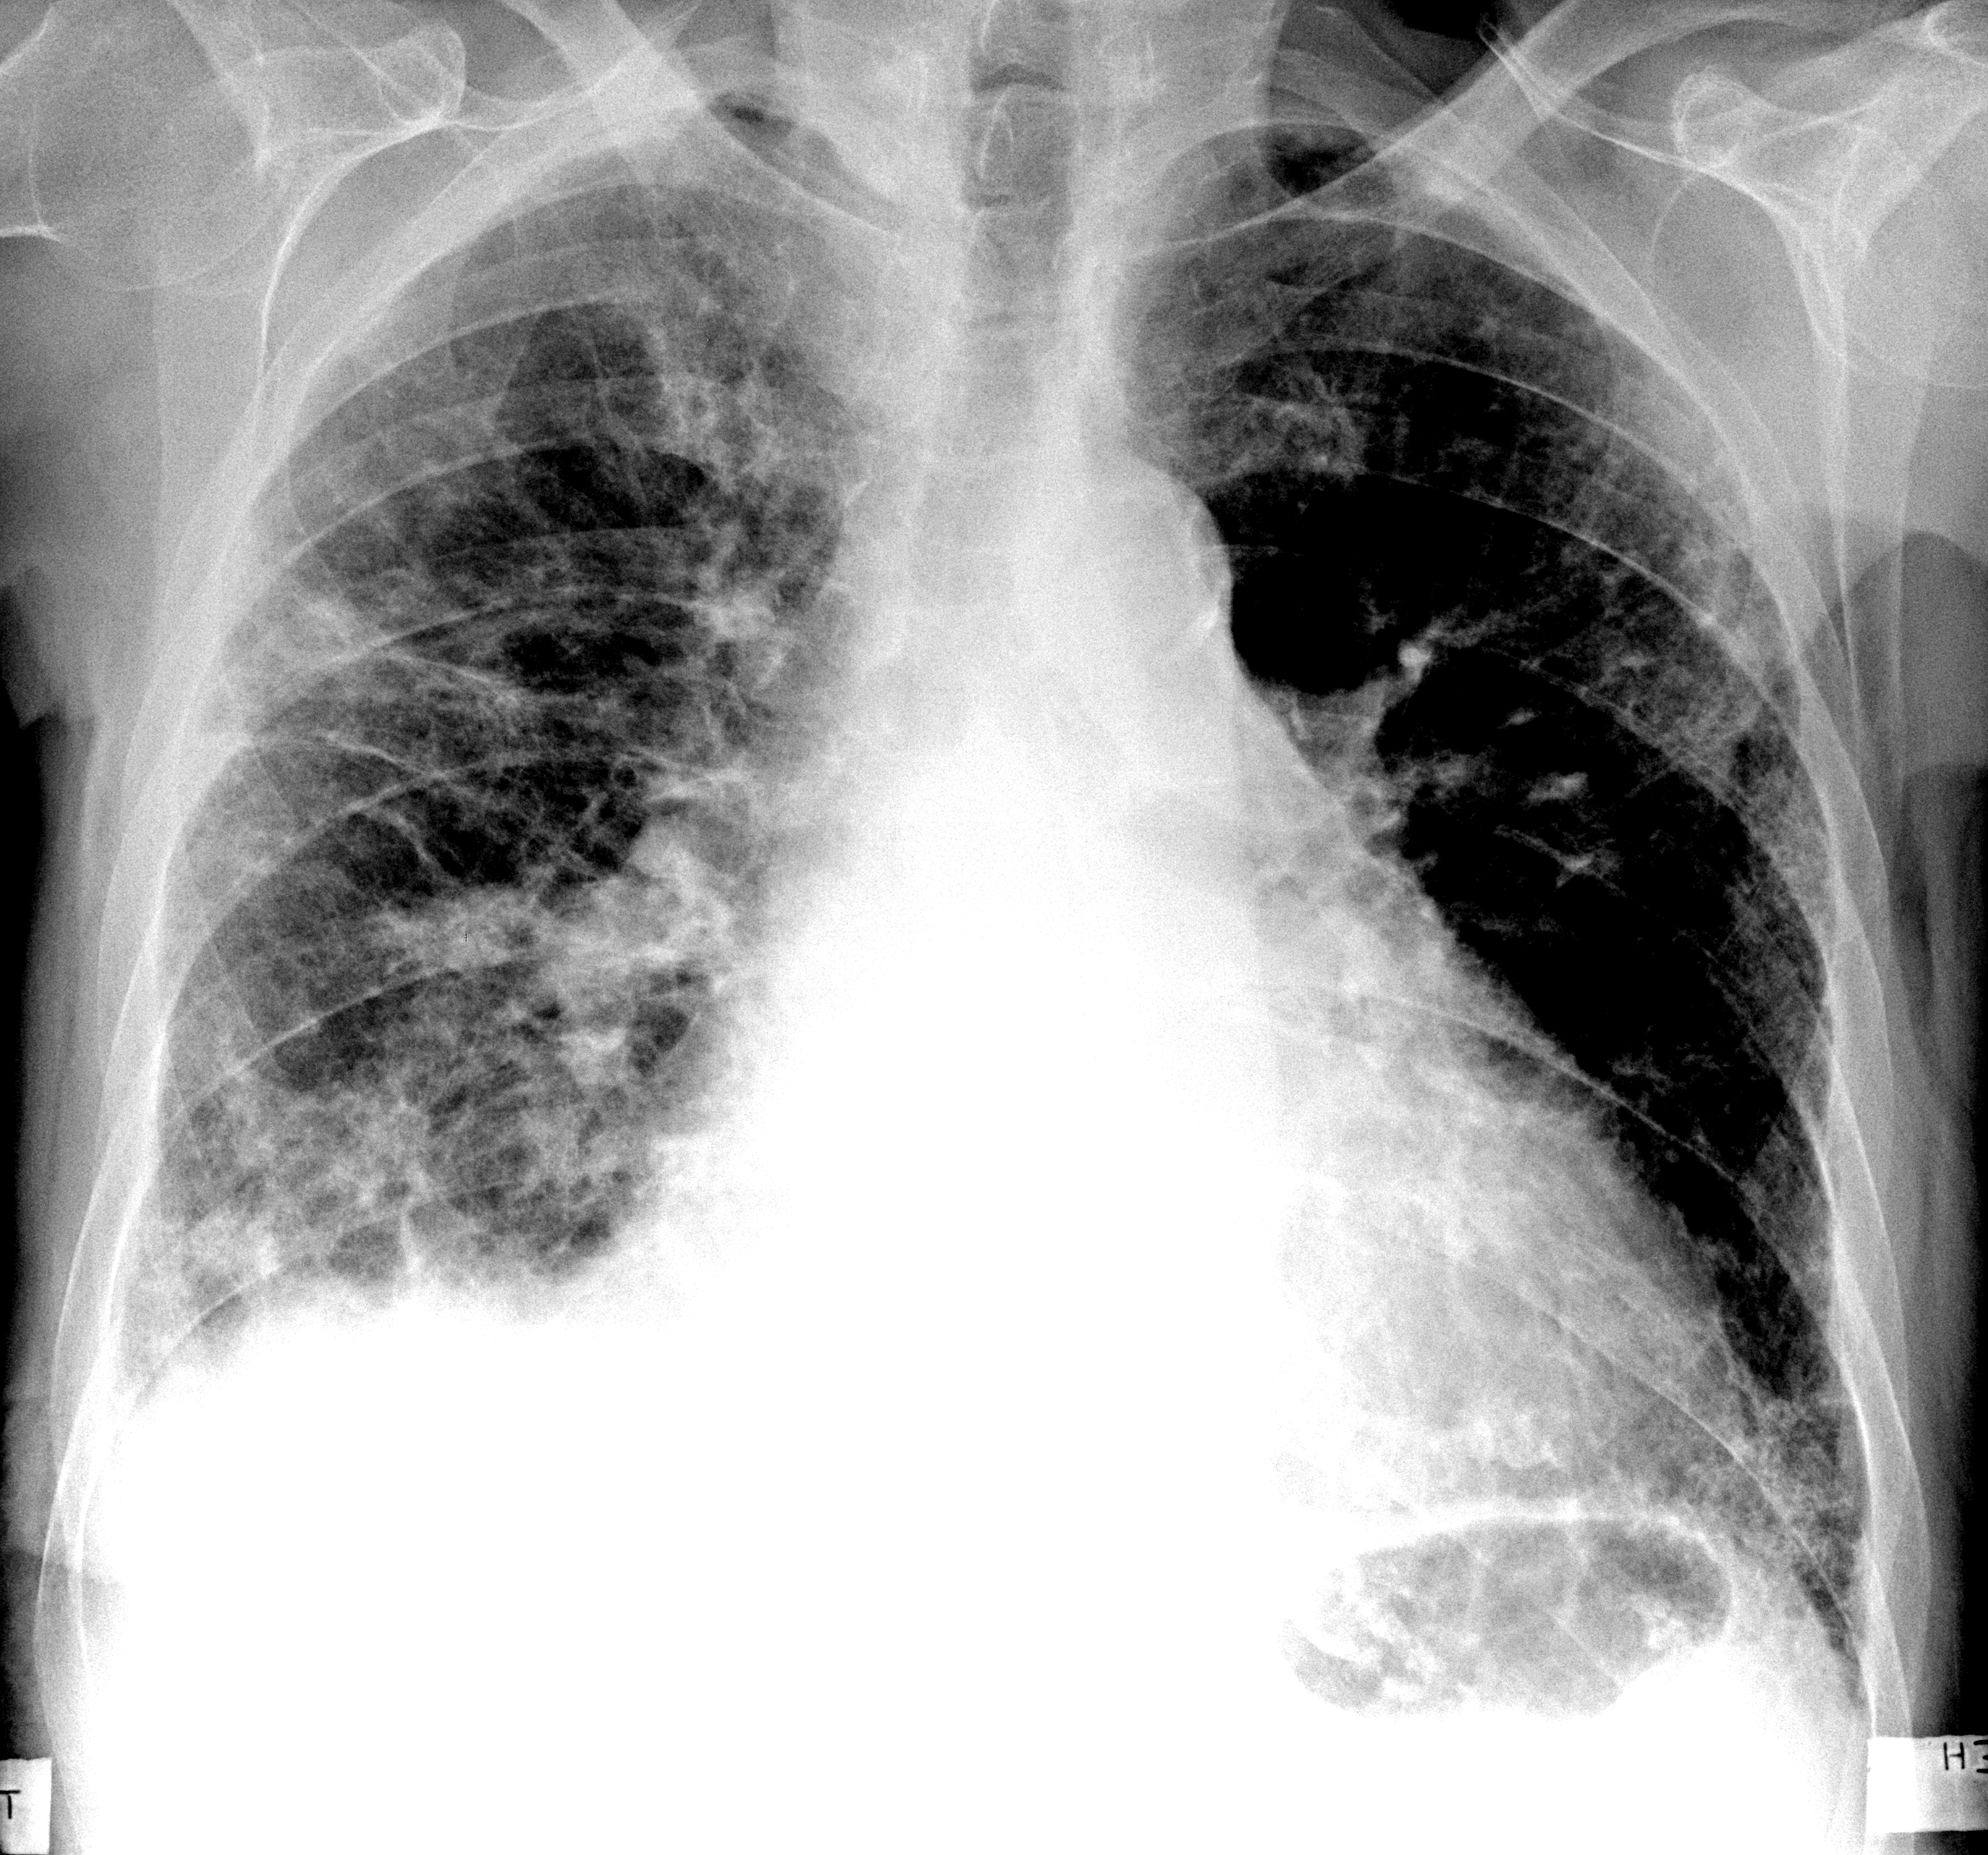

Рентгенологические изображения и синдромы патологии легких

Раздел: Кадры-подсказки